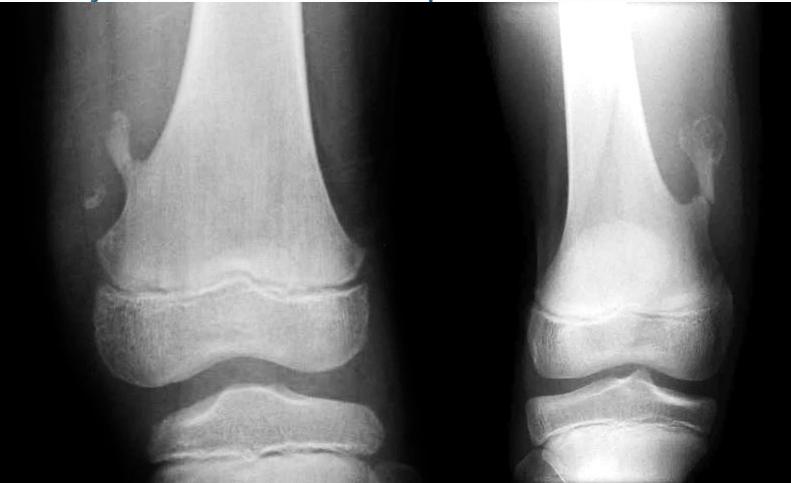

Non-ossifying fibroma …Fibrous cortical defect

Aneurysmal Bone Cyst

- Child - young adult

- Metaphysis of long bone

- X-ray:

- Well-defined cyst

- Trabeculated

- Eccentrically placed

- Ballooning

- Bloody content

- Treatment:

- Curettage and bone graft

- Metaphysis, Eccentric

Comparison of Cyst-Like Lesions in Bone

Simple Bone Cyst

- Fills medullary cavity

- Does not expand bone

- At metaphyseal side of physis

- Expansile

Giant-Cell Tumor

- After fusion of physis

- Extend to sub-articular